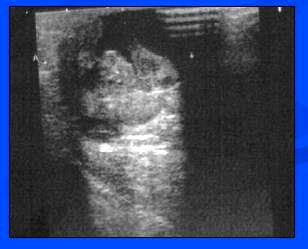

- UZ – heterogenní lehce hypoech. Ložisko s anechogen. Cystickými porcemi

- Dg. – susp.absces, intracyst.tumor?

- CCB HI – obraz nekrózy s naznačeně granulomatózní okolní zánětlivou reakcí

- Rozpor mezi klinickým nálezem a z CCB benigní histologií